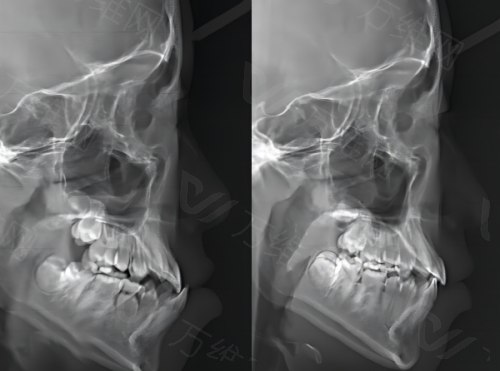

医院引进了国内外精良的口腔诊疗设备,如数字化口腔扫描仪、口腔CT等。数字化口腔扫描仪能够快速、正确地获取患者口腔的三维数据,为后续的治疗提供严谨的模型。口腔CT则可以清晰地显示口腔内部的结构,帮助医生更正确地诊断病情。这些精良的设备使得医院的诊断和治疗更加精细、效率高,大大提高了治疗的成功几率。相比一些当地小医院,设备的精良性是美冠塔的一大优势。